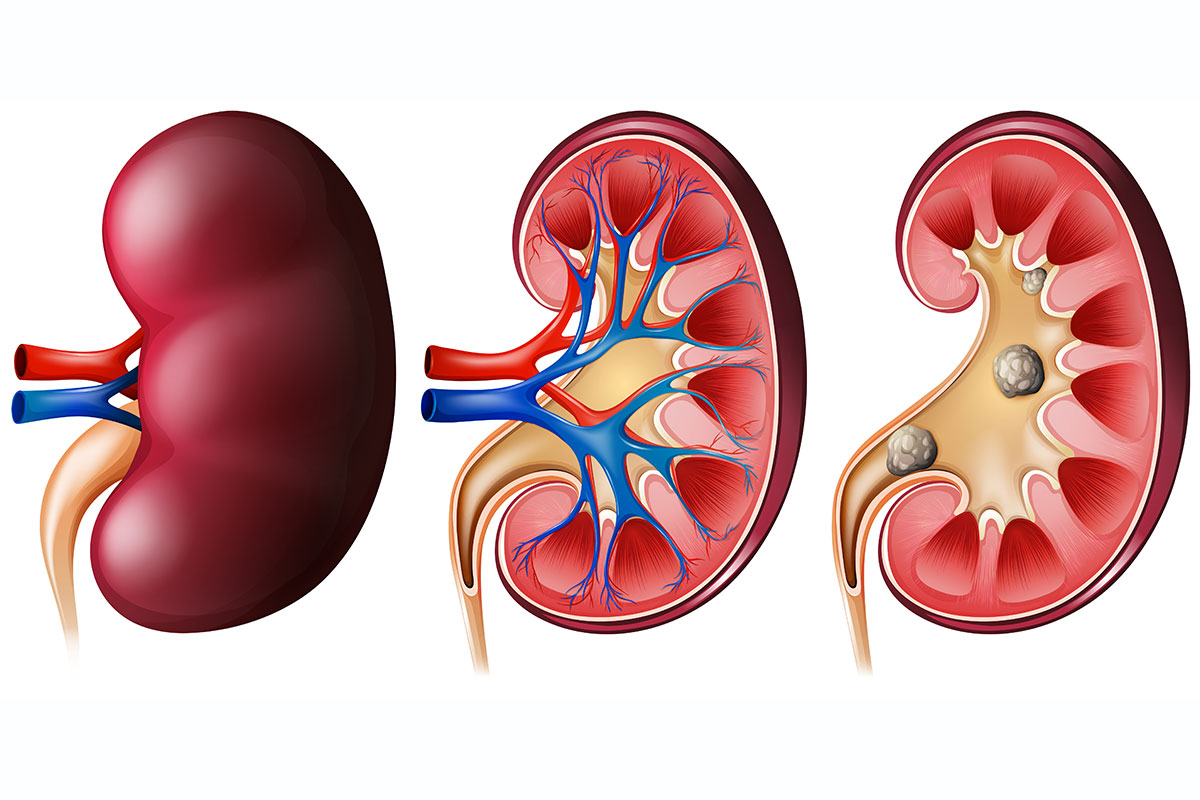

Строение почек человека: Фото и описание